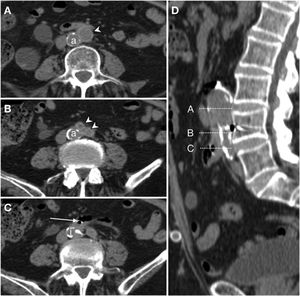

Graft erosion in a 61-year-old male with a history of aortobifemoral bypass surgery who presented long-standing fever, chills, weakness and persistent bacteraemia. Due to suspicion of graft infection, a CT scan was performed with IVC in the portal phase (A–C) which revealed perigraft oedema and parietal thickening of the third segment of the duodenum (*) encompassing the right iliac branch of the bypass in the absence of a fat plane achieving separation. Sagittal reconstruction (D) represented the level of the axial slices and coronal reconstruction (E) supported the findings reported. Extravasation of IVC was not observed. SPECT with marked leukocytes (F, G) showed radiotracer accumulation, and a PET/CT scan (H) revealed an increase in metabolic activity in the region proximal to the graft. These findings were suggestive of infection. Surgery (I) demonstrated the presence of graft erosion (dashed ellipse).